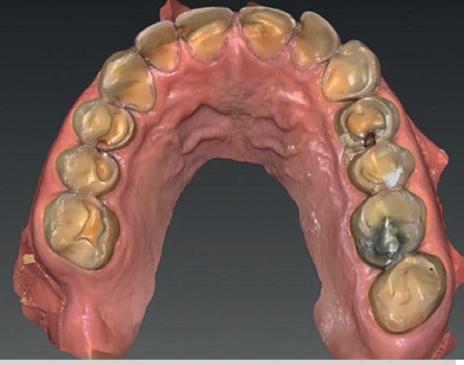

• Intra-orale scan voor studiemodellen, proefopstelling en beoordelen ruimte palatinaal

Vervaardigen essix retainer met dummies waarbij er een emergence profile van de 11 en 21 werd gevormd door eivormige dummies 4 mm in de gingiva te plaatsen

Na 4 weken intra-orale scan voor de etsbrug en kleurbepaling bij de technicus

Voordat er gescand kon worden voor een etsbrug, werd een studiemodel vervaardigd om met de technicus te overleggen of er voldoende ruimte was voor 2 centrale incisieven in de mesio-distale zin en of er voldoende ruimte was in occlusie voor de vleugels van de etsbrug. Er hoeft enkel nog aan de 12 en 22 pala-

tinaal geslepen te worden als er geen 1,5 mm ruimte voor de vleugels behaald kan worden. De ruimte was op de dunste plekken 1 mm, dus een kleine preparatie in de 12 en 22 palatinaal was nodig. Omdat de kaak volledig afgevlakt was en dun was geworden, kunnen de dummies van de etsbrug enkel op de kaak “gelegd worden”, maar daarbij zijn er geen papillen en staat de cervicale rand van de dummies net voor de kaak. Een esthetisch resultaat kan daarmee niet behaald worden. Daarom is een aanvulling van de zachte weefsels in de breedte nodig, als het creëren van een emergence profile, waarbij het oogst alsof de gebitselementen uit het weefsel vertrekken.